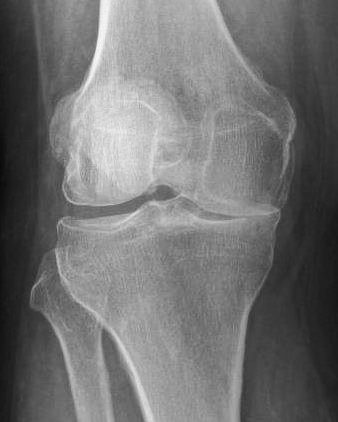

X-ray will show joint space narrowing on one side.

From the planning X-rays surgeon will determine what degree of new angulation is required, and whether this can be achieved by opening a gap and allowing new bone to fill the space ('opening-wedge' HTO) or by removing a wedge and fixing the two bony edges together and allowing them to unite ('closing-wedge' HTO).